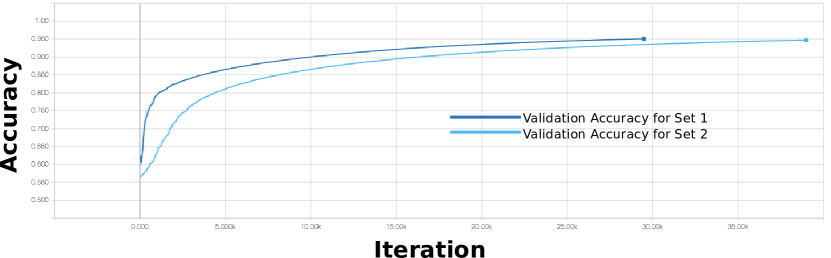

We empirically derived the parameters using a two-fold cross-validation approach on the training data (see Section II-A). Table I lists the parameters used for our training. Further information on our parameter validation is provided in Section SI of the Supplementary Materials.

Table II shows the comparison of our co-learning CNN with the baseline fusion methods on ROI detection and segmentation experiments. The data are presented individually for each of the three ROI, for all foreground ROI collectively, and separately for the non-ROI ‘other’ region. In the detection experiments, our co-learning method has higher mean accuracy when compared to all baselines for all individual ROIs and for the foreground. The improvement in accuracy offered by our method is statistically significant () for all ROIs. In ROI and foreground detection, our co-learning fusion method improves upon all baselines in 15 of the 16 metrics and 14 of these improvements are statistically significant compared to all baselines (all 15 improvements are statistically significant over at least one baseline). The largest overall improvement was in the precision metric, indicating that our method resulted in an increase in the ratio of true positives to false positives. In the segmentation experiments, our co-learning CNN had a significantly higher Dice score () than all baseline fusion CNNs for all foreground ROIs individually and collectively.

SI Verification of Parameter Settings